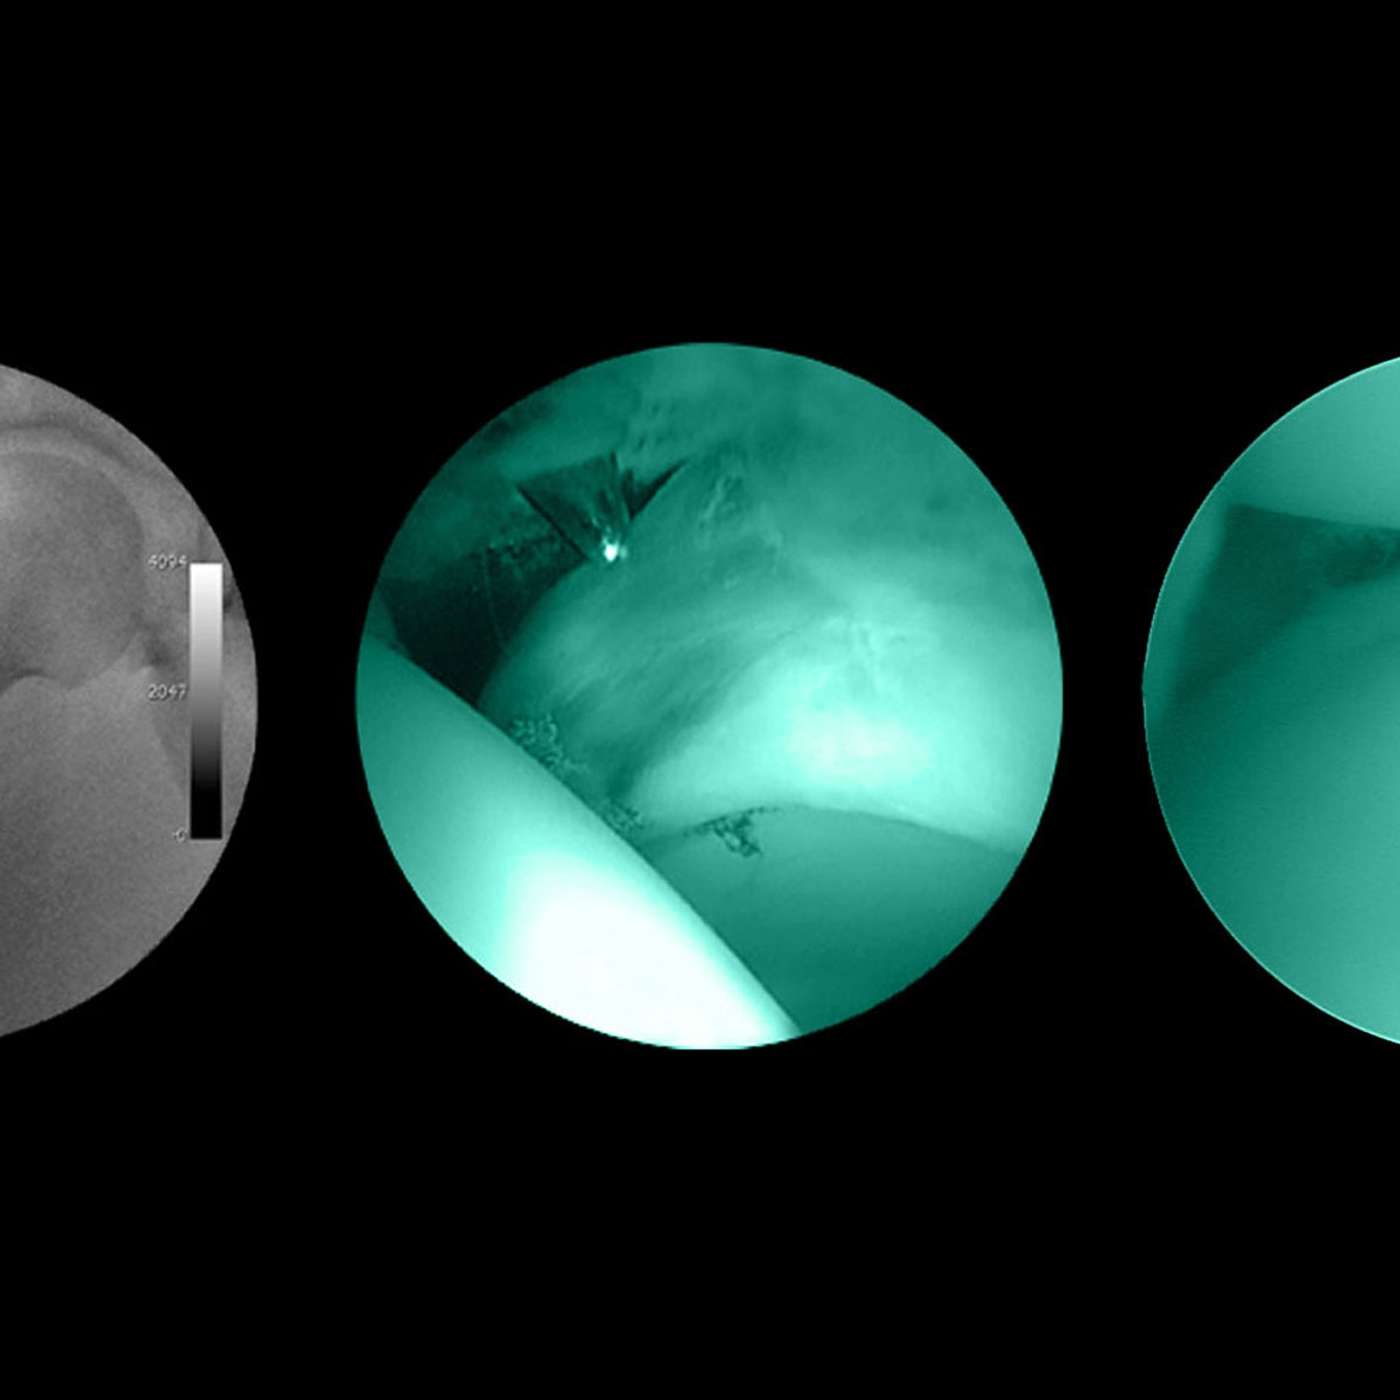

This lecture examines how minimal access ('keyhole') surgery has revolutionised medicine in just a few decades. By re-assembling teams of long-retired surgical pioneers from the 1980s and inviting them to re-enact early procedures using realistic simulation it will document the ups and downs of an extraordinary decade.

Using video footage and interviews, Professor Kneebone will show how surgeons, radiologists, nurses and instrument manufacturers developed completely new ways of working. Their successes, their failures and their challenges continue to resonate today.